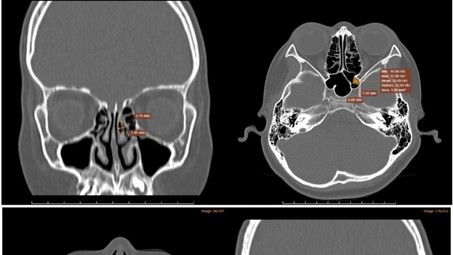

Hình ảnh chụp CT-Scanner xoang phát hiện tình trạng viêm đa xoang hàm mặt.

Kết quả chụp CT-Scanner xoang cho thấy hình ảnh viêm đa xoang hàm mặt, dày nhẹ niêm mạc cuốn mũi dưới hai bên, polyp xoang bướm trái, xoang hơi cuốn mũi giữa bên trái. Hình ảnh nội soi mũi phát hiện tình trạng viêm mũi xoang dị ứng.